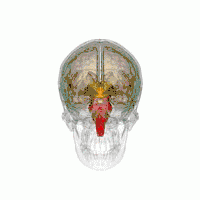

Les principales régions du cerveau affectées par la PSP sont les suivantes :

- le tronc cérébral, en particulier la partie du mésencéphale où réside le mouvement « supranucléaire » de l'œil, ainsi que les noyaux dopaminergiques ;

- les ganglions de la base, en particulier le noyau sous-thalamique, la substance noire (ou locus niger) et le globus pallidus ;

- le cortex cérébral, en particulier la zone des lobes frontaux ;

- le noyau dentelé du cervelet (le cervelet représente un bon 50 % de nos neurones) ;

- et la moelle épinière, en particulier la zone où sont commandés certains contrôles de la vessie et de l'intestin.